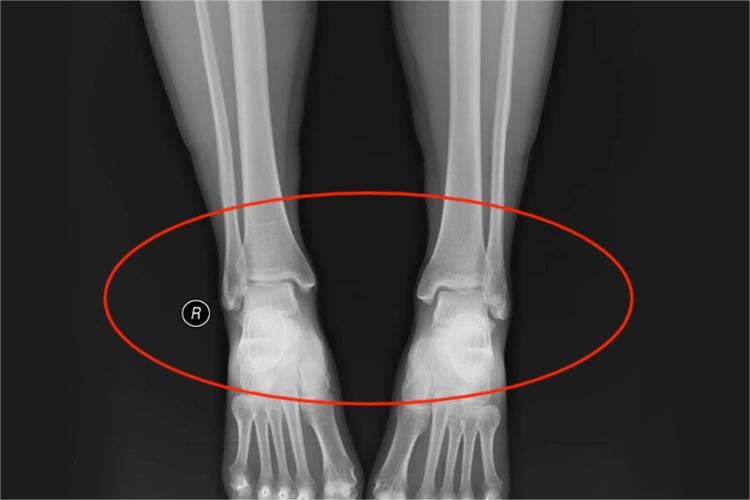

踝关节正位为踝关节的正位投影像,可显示踝关节间隙、部分跗骨间关节、部分跗跖关节间隙、以及关节构成、骨质和软组织情况。正常情况下,关节面呈切线位,关节间隙、诸骨小梁显示清晰,周围软组织层次分明,影像层次丰富,对比良好,无明显伪影。